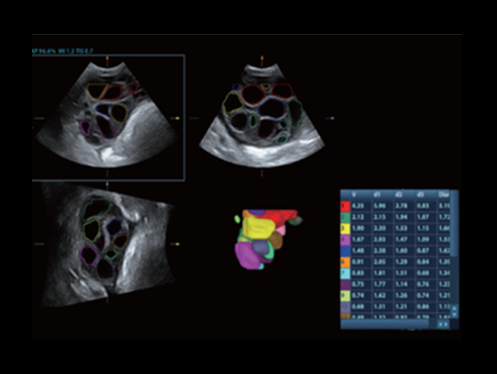

Inteligencia eXcepcional

Inteligencia a lo largo de todo el flujo de trabajo

El ecГіgrafo DC-80A con X-Insight proporciona una soluciГіn excepcionalmente inteligente para la completa salud de la mujer, desde fertilidad hasta el cribado prenatal y asistencia sanitaria posparto.